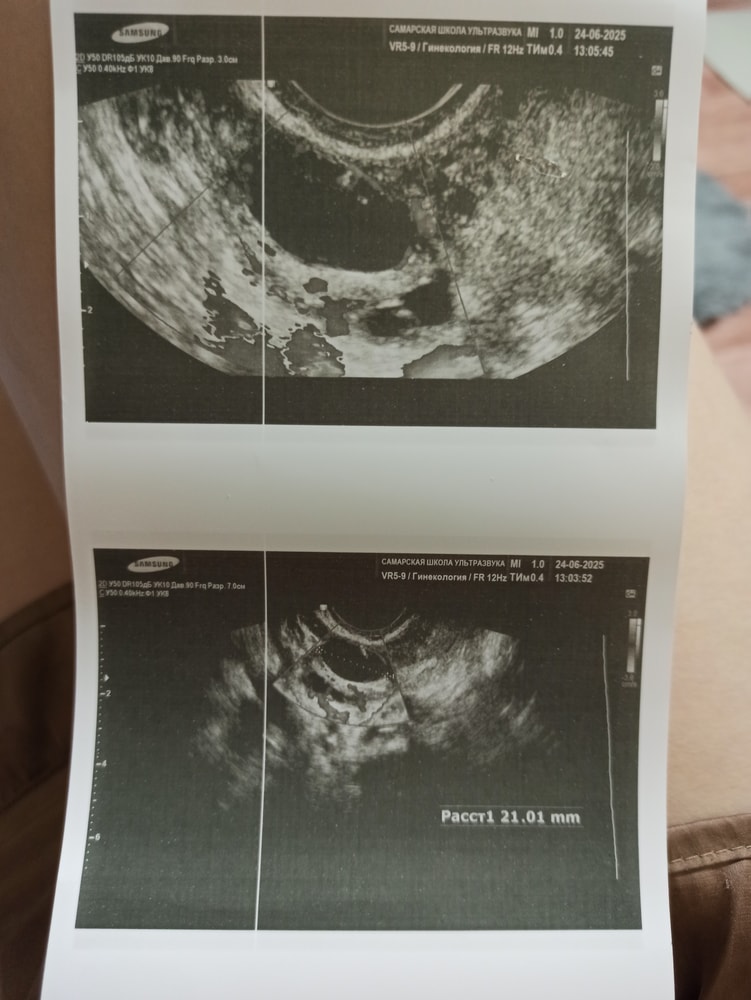

Девочки, скажите, пожта, могли ли пепутать желтое тело с дф?

Я вчера был на УЗИ и мне показывали на экране в одном яичнике жёлтое тело, в другом крупные фолликулы до 15 мм. Жёлтое тело было как будто заполненное чем то, там видно кровоток вокруг, а фолликулы круглые и пустые)

У вас похоже на фолликул в процессе овуляции.

Это дф. Жт выглядит немного иначе.

Екатерина, спасибо а что за кровоток тогда у доминантоного фолликкла?

Александра Токарева, так у узиста спросите. Возможно это не дф, а киста вообще.

Екатерина, она убежденно говорила, что жт, ранее была у нее месяц назад, там вообще тизо было.